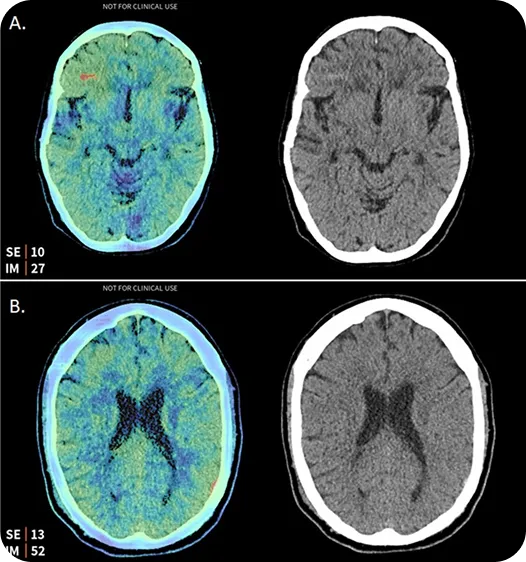

Aidoc si integra perfettamente nei sistemi ospedalieri e nelle liste di lavoro dei radiologi, dove aiuta a identificare condizioni urgenti come embolie polmonari ed emorragie intracraniche. Dando priorità ai casi di emergenza, Aidoc supporta una risposta clinica più rapida senza interrompere i flussi di lavoro esistenti.

Fig. 3. Emorragie intracraniche rilevate da Aidoc. (Fonte)